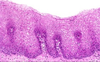

Describe this pathology

GERD

acid-pepsin injury increases cell death and desquamation at surface, w/ compensatory basal hyperplasia (+ elongated submucosal rete pegs)